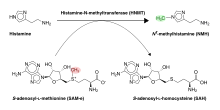

Specifically, HNMT transfers a methyl (CH3) group from S-adenosyl-L-methionine (SAM-e) to histamine, forming an inactive metabolite called Nτ-methylhistamine, in a chemical reaction called Nτ-methylation. In mammals, HNMT operates alongside diamine oxidase (DAO) as the only two enzymes responsible for histamine metabolism; however, what sets HNMT apart is its unique presence within the central nervous system (CNS), where it governs intracellular histaminergic neurotransmission. By degrading and regulating levels of intracellular histamine specifically within the CNS, HNMT ensures the proper functioning of neural pathways related to arousal, sleep-wake cycles, and other essential brain functions.

The function of the HNMT enzyme is histamine metabolism by ways of Nτ-methylation using S-adenosyl-L-methionine (SAM-e) as the methyl donor, producing Nτ-methylhistamine, which, unless excreted, can be further processed by monoamine oxidase B (MAOB) or by DAO. Methylated histamine metabolites are excreted with urine.[12][13][11]

Nτ-methylhistamine (NMH), also known as 1-methylhistamine, is a product of Nτ-methylation of histamine in a reaction catalyzed by the HNMT enzyme.[24][12][13]